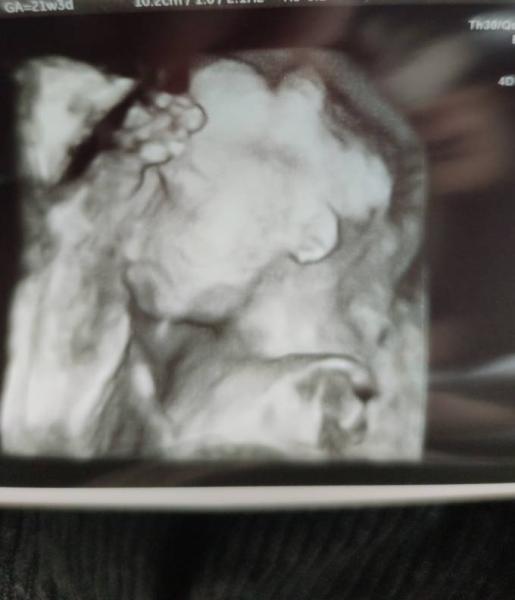

Ein süßes 3D Bild haben wir auch noch bekommen, auch wenn der kleine sein Gesicht immer in meinem Becken verstecken wollte.